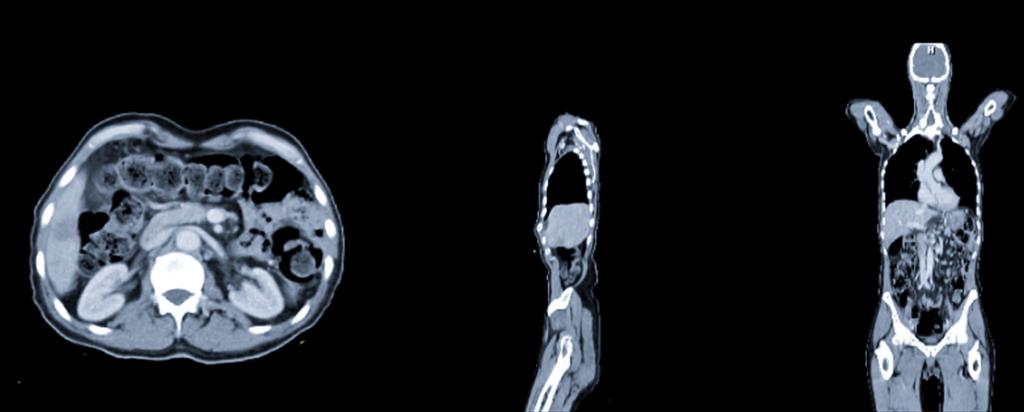

PET is a nuclear medicine imaging technique in which a small amount of radioactive material is injected into the body and is used to diagnose a variety of diseases, including many types of cancers.